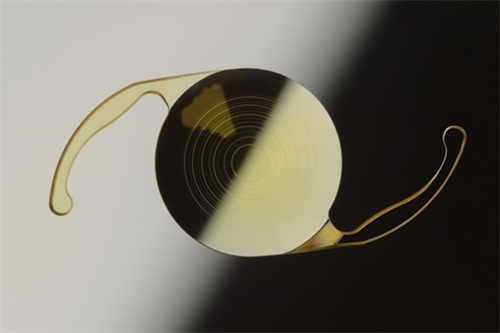

人工晶体植入术(ICL)通过在眼内植入一个特殊的人工晶体来矫正视力,这种手术避免了切削角膜的风险,且对角膜厚度没有严格要求。对于近视度数高达1500度的患者来说,这种手术方式可能更为适合。ICL手术适应的近视度数范围广泛,通常可矫正300度到2300度的近视,以及600度以下的散光。